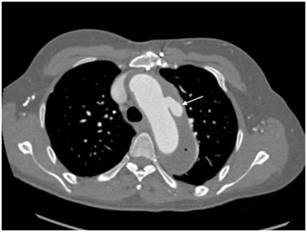

Figura 5 Caso de disección aórtica Stanford B/De Bakey 3. Paciente masculino de 50 años de edad con disección aórtica Stanford tipo B/De Bakey tipo 3. La flecha negra indica el colgajo de disección que inicia distal a la arteria subclavia izquierda. La flecha blanca indica la luz falsa trombosada.

(6.7% de la muestra) en comparación con Stanford B (1.8% de la muestra), similar a lo observado en nuestro estudio15. El 53.1% de los pacientes tuvieron antecedente de aneurisma aórtico; se encontró asociación significativa de aneurismas de aorta abdominal con los subtipos de DA según la clasificación de Stanford (p = 0.047104). Así mismo, se encontró incidentalmente un caso con úlcera penetrante en el cayado en un paciente con aneurisma de aorta torácica con trombo mural asociado (fig. 6). La úlcera penetrante es, junto con la DA y el hematoma intramural, una de las patologías que componen el síndrome aórtico agudo, y consiste en la ulceración de placas ateroescleróticas que pueden llevar

a hematoma intramural, disección o perforación aórtica15. La mortalidad general a 6 meses en los pacientes con

Figura 6 Caso de disección aórtica Stanford B/De Bakey 3. Paciente femenino de 53 años de edad con disección aórtica Stanford tipo B/De Bakey tipo 3. La flecha blanca indica úlcera penetrante en el cayado aórtico, mientras que el asterisco (*) indica el trombo mural.